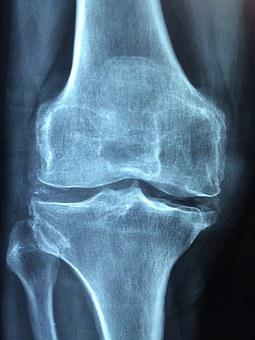

관절염의 경우 뼈 마디마디에 발생할 수 있으며 발생부위가 다 다르기 때문에 통증이 있는 곳의 정밀검사를 시행합니다

mri를 찍어 관절의 연골이 닳아있는지 , 인대파열이 동반되었는지 를 판단하며 상태가 심할 경우 인공관절 수술을 시행할 수 있습니다 초기에는 주사 또는 물리치료로 치료를 하며 무릎관절염의 경우 예방차원으로 매일 한 시간 정도를 걸어주시는 게 좋다고 합니다 이렇게 걷기 운동을 해주시면 허벅지근육이 강화되면서 무릎관절을 보호해 주고 예방할 수 있다고 합니다